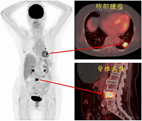

使用去氧葡萄糖全身正子掃描在診斷及治療癌症上的幫助(相關圖片)> 此病人最近半年飽受體重減輕及下背痛困擾,前來求診並進行健康檢查

> 去氧葡萄糖正子掃描發現除了在後背疼痛處發現高葡萄糖代謝骨骼病灶之外,另外也在左肺發現有呈現葡萄糖攝取增加的肺部腫瘤及肺門淋巴結。根據正子掃描的結果,顯示可能是惡性腫瘤併發轉移的現象